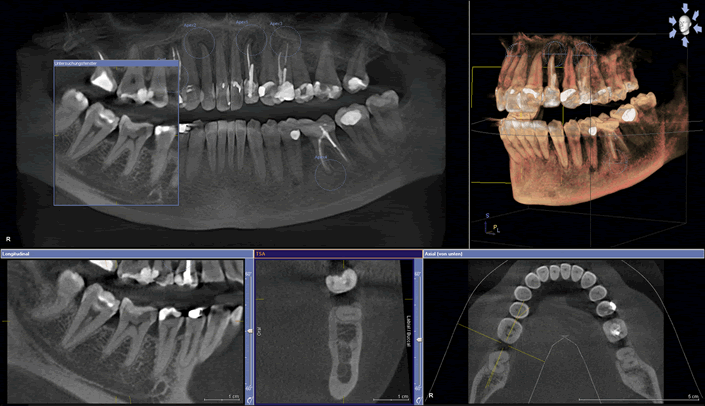

Using this we then take a cone beam CT scan.

This scan allows us to see:

A cone beam is seen by all experience implant surgeons as a crucial step in implant dentistry.